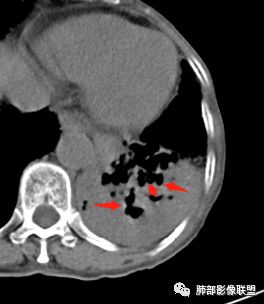

这些支气管扩张

支气管有扩张

支气管扩张、扭曲成团,附近钙化灶

这例左下叶的体积是整体缩小的,左下叶的支气管主干稍微小一点点,然后左上叶的下舌段也有类似的病灶,然后我们看到一团乱的支气管扩张,但它有特点,边缘凹凸不平。那什么样的支气管扩张边缘会如此凹凸不平呢,等我截个图:

首先这幅图支气管很多地方是扭曲的,远端扩张的特别厉害。如果是肿瘤,首先考虑淋巴瘤,因为支气管可直达远端,稍扩张,但是它的前提是周围要实性占位的,而且它不会这样扭曲变形。我们看这个病例的支气管扩张,它支气管扩张占大部分区域,中间稍有些实性的结构,这就不符合了。这幅图你会发现所有支气管都是扩张的,实性部分偏少,外围胸水。所以我更倾向慢性炎性病变,能够引起支气管扩张的炎性病变有哪些?结核?NTM?支扩伴感染?大方向是慢性炎性病变。这些左下肺播散出来的病灶,咳中等量黄浓痰,我考虑还可能合并细菌感染。